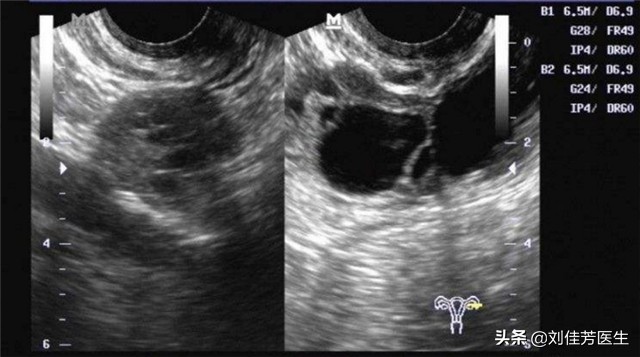

5、积液不通

输卵管发炎后,就会形成炎症积液。时间一长,这些炎症积液很可能会影响到输卵管通畅。女性如果患有这种输卵管积液造成的不通的话,平时会有小腹发凉的感觉。在月经经期内,会有明显的小腹坠痛感。输卵管积液不通没有得到妥善的治疗的话,很可能引起宫颈糜烂、盆腔炎等等妇科疾病。